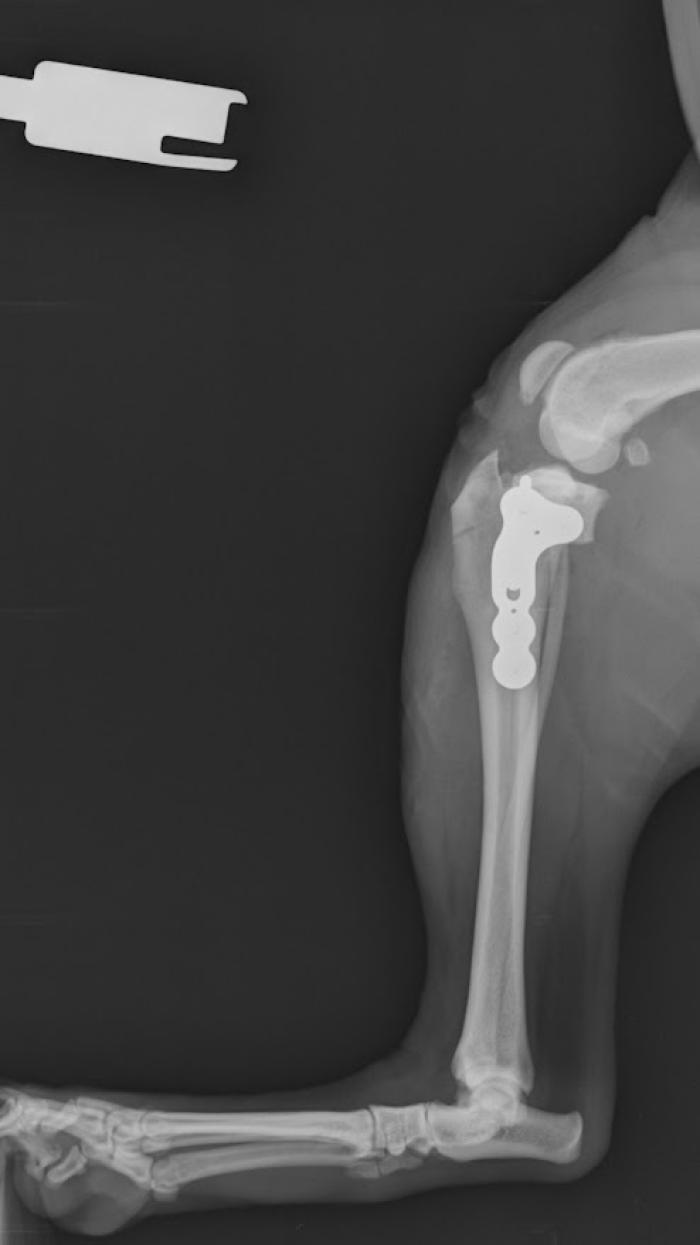

El ligamento de polietileno ultrarresistente de ultra alto peso molecular, se fija mediante tornillos interferenciales de titanio (Figura 2).

- las fibras libres: posicionamiento de las fibras libres (Figura 3),